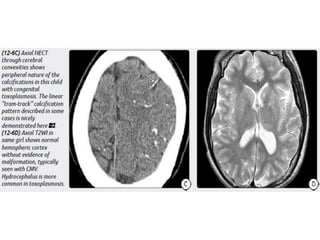

Congenital Toxoplasmosis

Imaging

Scattered parenchymal calcifications.

Multiple subcortical cysts.

Porencephaly.

Ventriculomegaly (hydrocephalus) often due to inflammatory debris and

aqueductal obstruction.

Lack of cortical malformations.

Congenital (Perinatal) HIV

Atrophy, particularly in the frontal lobes.

Bilaterally symmetric basal ganglia calcifications.

Ectasia and fusiform enlargement of intracranial arteries.

Strokes with foci of restricted diffusion and subarachnoid hemorrhage

may occur as complications of the underlying vasculopathy.